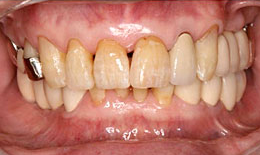

治療後

治療の流れ

1. はじめに、順番にインプラントを入れていきます。

2. その後、全部の歯を、仮歯に置き換えます。

3. 全体で、上下左右のバランスをとりながら、しばらくの間使っていただいて、仮歯が割れたり、取れたりしないようになって落ち着いてから、最終的な被せに変え、最後にマウスピースを使っていただいて完成です。